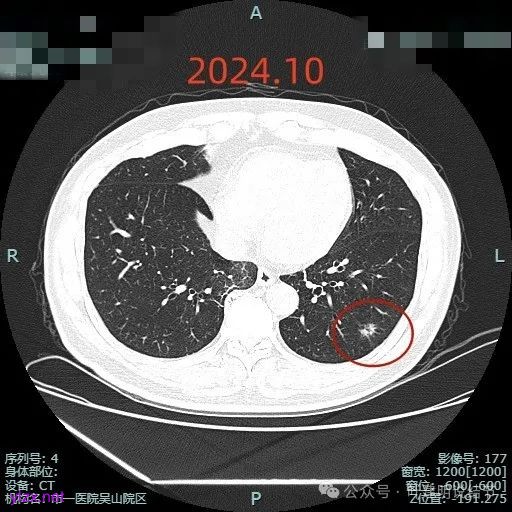

再看2024年10月时复查时我的意见:

对比至少没有进展,密度似略减低,考虑慢性炎伴纤维增生可能性大。